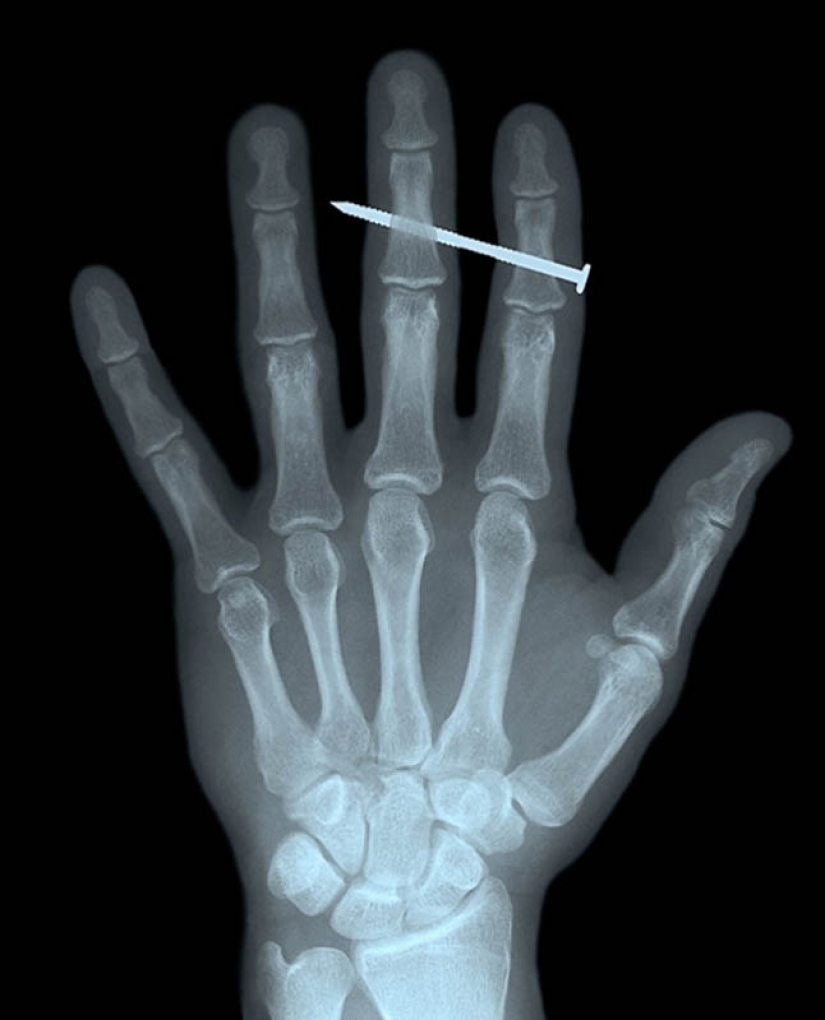

4. El clavo en los huesos de los dedos índice y medio de hombres adultos.